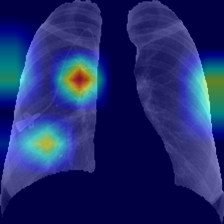

III-E Identification of the areas of significant interest for the classification

The areas of significant interest used by the CNN for discrimination purposes are identified using a qualitative analysis based on a Gradient-weighted Class Activation Mapping (Grad-CAM) [38]. This is an explainability method that serves to provide insights about the manners on how deep neural networks learn, pointing to the most significant areas of interest for decision-making purposes. The method uses the gradients of any target class to flow until the final convolutional layer, and to produce a coarse localization map which highlights the most important regions in the image identifying the class. The result of this method is a heat map like those presented in Fig. 1, in which the colour encodes the importance of each pixel in differentiating among classes.

The regions of interest identified by the network, were analyzed qualitatively using Grad-CAM activation maps [38]. Results shown by the activation maps, permit the identification of the most significant areas in the image, highlighting the zones of interest that the network is using to discriminate. In this regard, Fig. 1, presents examples of the Grad-CAM of a control, a pneumonia, and a COVID-19 patient, for each of the three experiments considered in the paper. It is important to note that the activation maps are providing overall information about the behaviour of the network, pointing to the most significant areas of interest, but the whole image is supposed to be contributing to the classification process to a certain extent.

The second row in Fig. 1 shows several prototipical results applying the Grad-CAM techniques to experiment 1. The examples show the areas of significant interest for a control, pneumonia and COVID-19 patient. The results suggest that the detection of pneumonia or COVID-19 is often carried out based on information that is outside the expected area of interest, i.e. the lung area. In the examples provided, the network focuses on the corners of the XR image or in areas around the diaphragm. In part, this is likely due to the metadata which is frequently stamped on the corners of the XR images. The Grad-CAM plots corresponding to the experiment 2 (third row of Fig 1), indicates that the model still points towards areas which are different to the lungs, but to a lesser extent. Finally, the Grad-CAM of experiment 3 (fourth row of Fig 1) presents the areas of interest where the segmentation procedure is carried out. In this case, the network is forced to look at the lungs, and therefore this scenario is supposed to be more realistic and more prone to generalizing as artifacts that might bias the results are somehow discarded.

We stand on the fact that automatic diagnosis is much more than a classification exercise, meaning that many factors have to be had in mind to bring these techniques to the clinical practice. To this respect, there is a classic assumption in the literature that the associated heat maps –calculated with techniques such as Grad-CAM– provide a clinical interpretation of the results, which is unclear in practice. In light of the results shown in the heat maps depicted in Fig. 1, we show that experiment 1 must be carefully interpreted. Despite the high-performance metrics obtained in experiment 1, the significant areas identified by the network are pointing towards certain areas with no clear interest for the diagnosis, such as corners of the images, the sternum, clavicles, etc. From a clinical point of view, this is clearly biasing the results. It means that other approaches are necessary to force the network to focus on the lungs area. To this respect, we have developed and compared the results with two preprocessing approaches based on cropping the images and segmenting the lungs area (experiment 2 and experiment 3). Again, given the heat maps corresponding to experiment 2, we also see similar explainability problems to those enumerated for experiment 1. Reducing the area of interest to that proposed in experiment 2 significantly decreases the performance of the system due to the removal of the metadata that usually appear in the top left and/or right corner, and to the removal of areas which are of interest to categorize the images but have no interest from the diagnosis point of view. However, while comparing experiment 2 and 3, performance results improve in the third approach, which focuses on the same region of interest but with a mask that forces the network to see only the lungs. Thus, results obtained in experiments 2 and 3 suggest that eliminating the needless features extracted from the background or non-related regions improves the results. Besides, the third approach (experiment 3), provides more explainable and interpretative results, with the network focusing its attention only in the area of interest for the disease. The gain in explainability of the last method is still at the cost of a lower accuracy with respect to experiment 1, but the improvement in explainability and interpretability are considered critical to translate these techniques to the clinical setting. Despite the decrease in performance, the proposed method in experiment 3 has provided promising results, with an Acc of , BAcc of , GMR of and AUC of .

The COVID-Net has also demonstrated being a good starting point for the characterization of the disease. Indeed, the outcomes of the paper suggest the possibility to automatically identifying the lung lesions associated with a COVID-19 infection (see Fig.1) by analyzing the Grad-CAM mappings of experiment 3, providing an explainable justification about the way the network works. However, the interpretation of the heat maps obtained for the control class must be carried out carefully. Whereas the areas of significant interest for pneumonia and COVID-19 classes are supposed to point to potential lesions (i.e. with higher density and/or with different textures in contrast to controls), the areas of significant interest for the classification in the control group are supposed to correspond to a sort of complement, potentially highlighting less dense areas. Thus, not meaning the presence of any kind of lesion in the lungs.